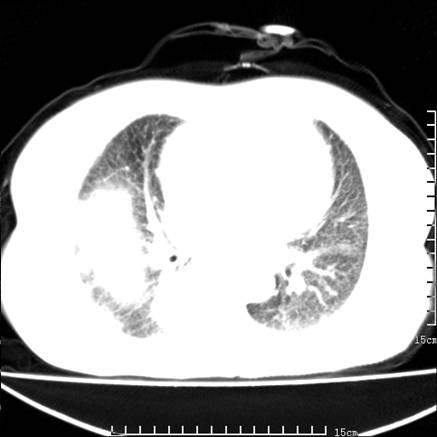

女,王某,58岁,咳嗽三个月余,基层医院二个月前诊为肺结核,用抗结核药二个月无明显疗效。

心包积液致肺瘀血.右侧周围型肺癌伴肺内转移,中间裂积液,叶间胸膜肥厚.右上肺大泡,右侧胸膜肥厚.

双肺继发型tb,心功能不全并肺淤血、心包、双侧叶间裂积液,肺大泡,右下胸膜肥厚钙化。